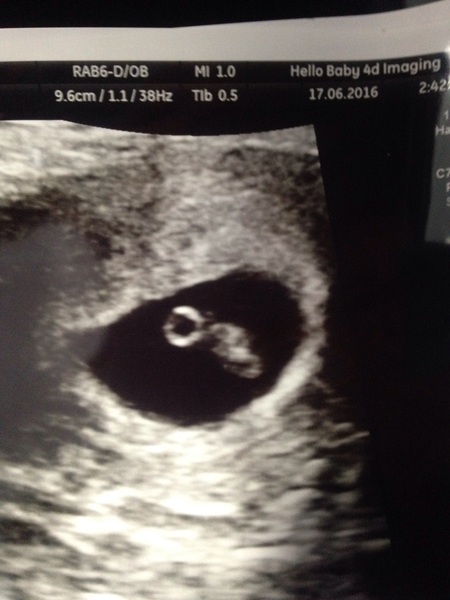

Hooray! Scan was good news, heartbeat of 130 and measuring 1cm, phew, can relax and enjoy the weekend a bit more now. Was dated for 2nd Feb.

I highly recommend having one if you can justify the extra cost... I went with babybond and the nurse was really lovely and professional

Our scan also went well. Saw the cutest little heart beat 😊 And measuring at 7.4mm :) back for another scan at 9+4 on 8th July x